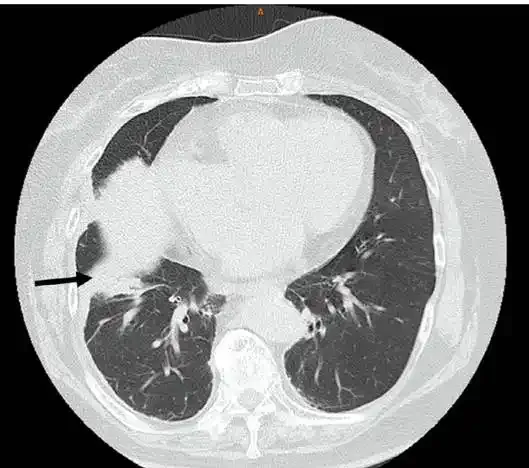

若出现以上症状应及时就医,完善检查:如血常规、C反应蛋白、肺部CT、胸部CT检查等相关检查,排除肺炎的可能。